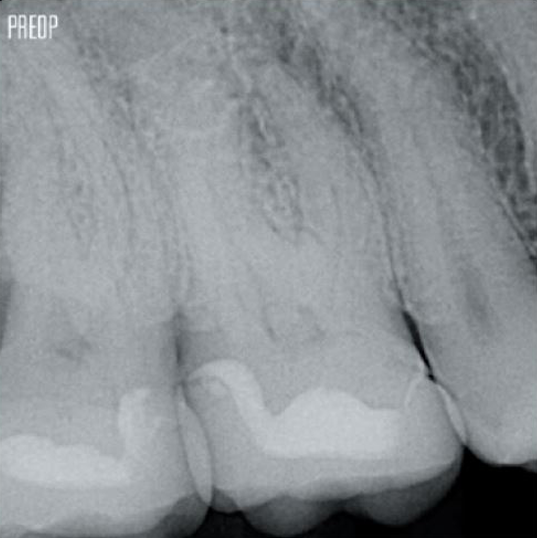

More dentin preserved. Appropiate shaping, irrigation, and obturation ensured.

Photos courtesy of Dr. Ahmed Salman